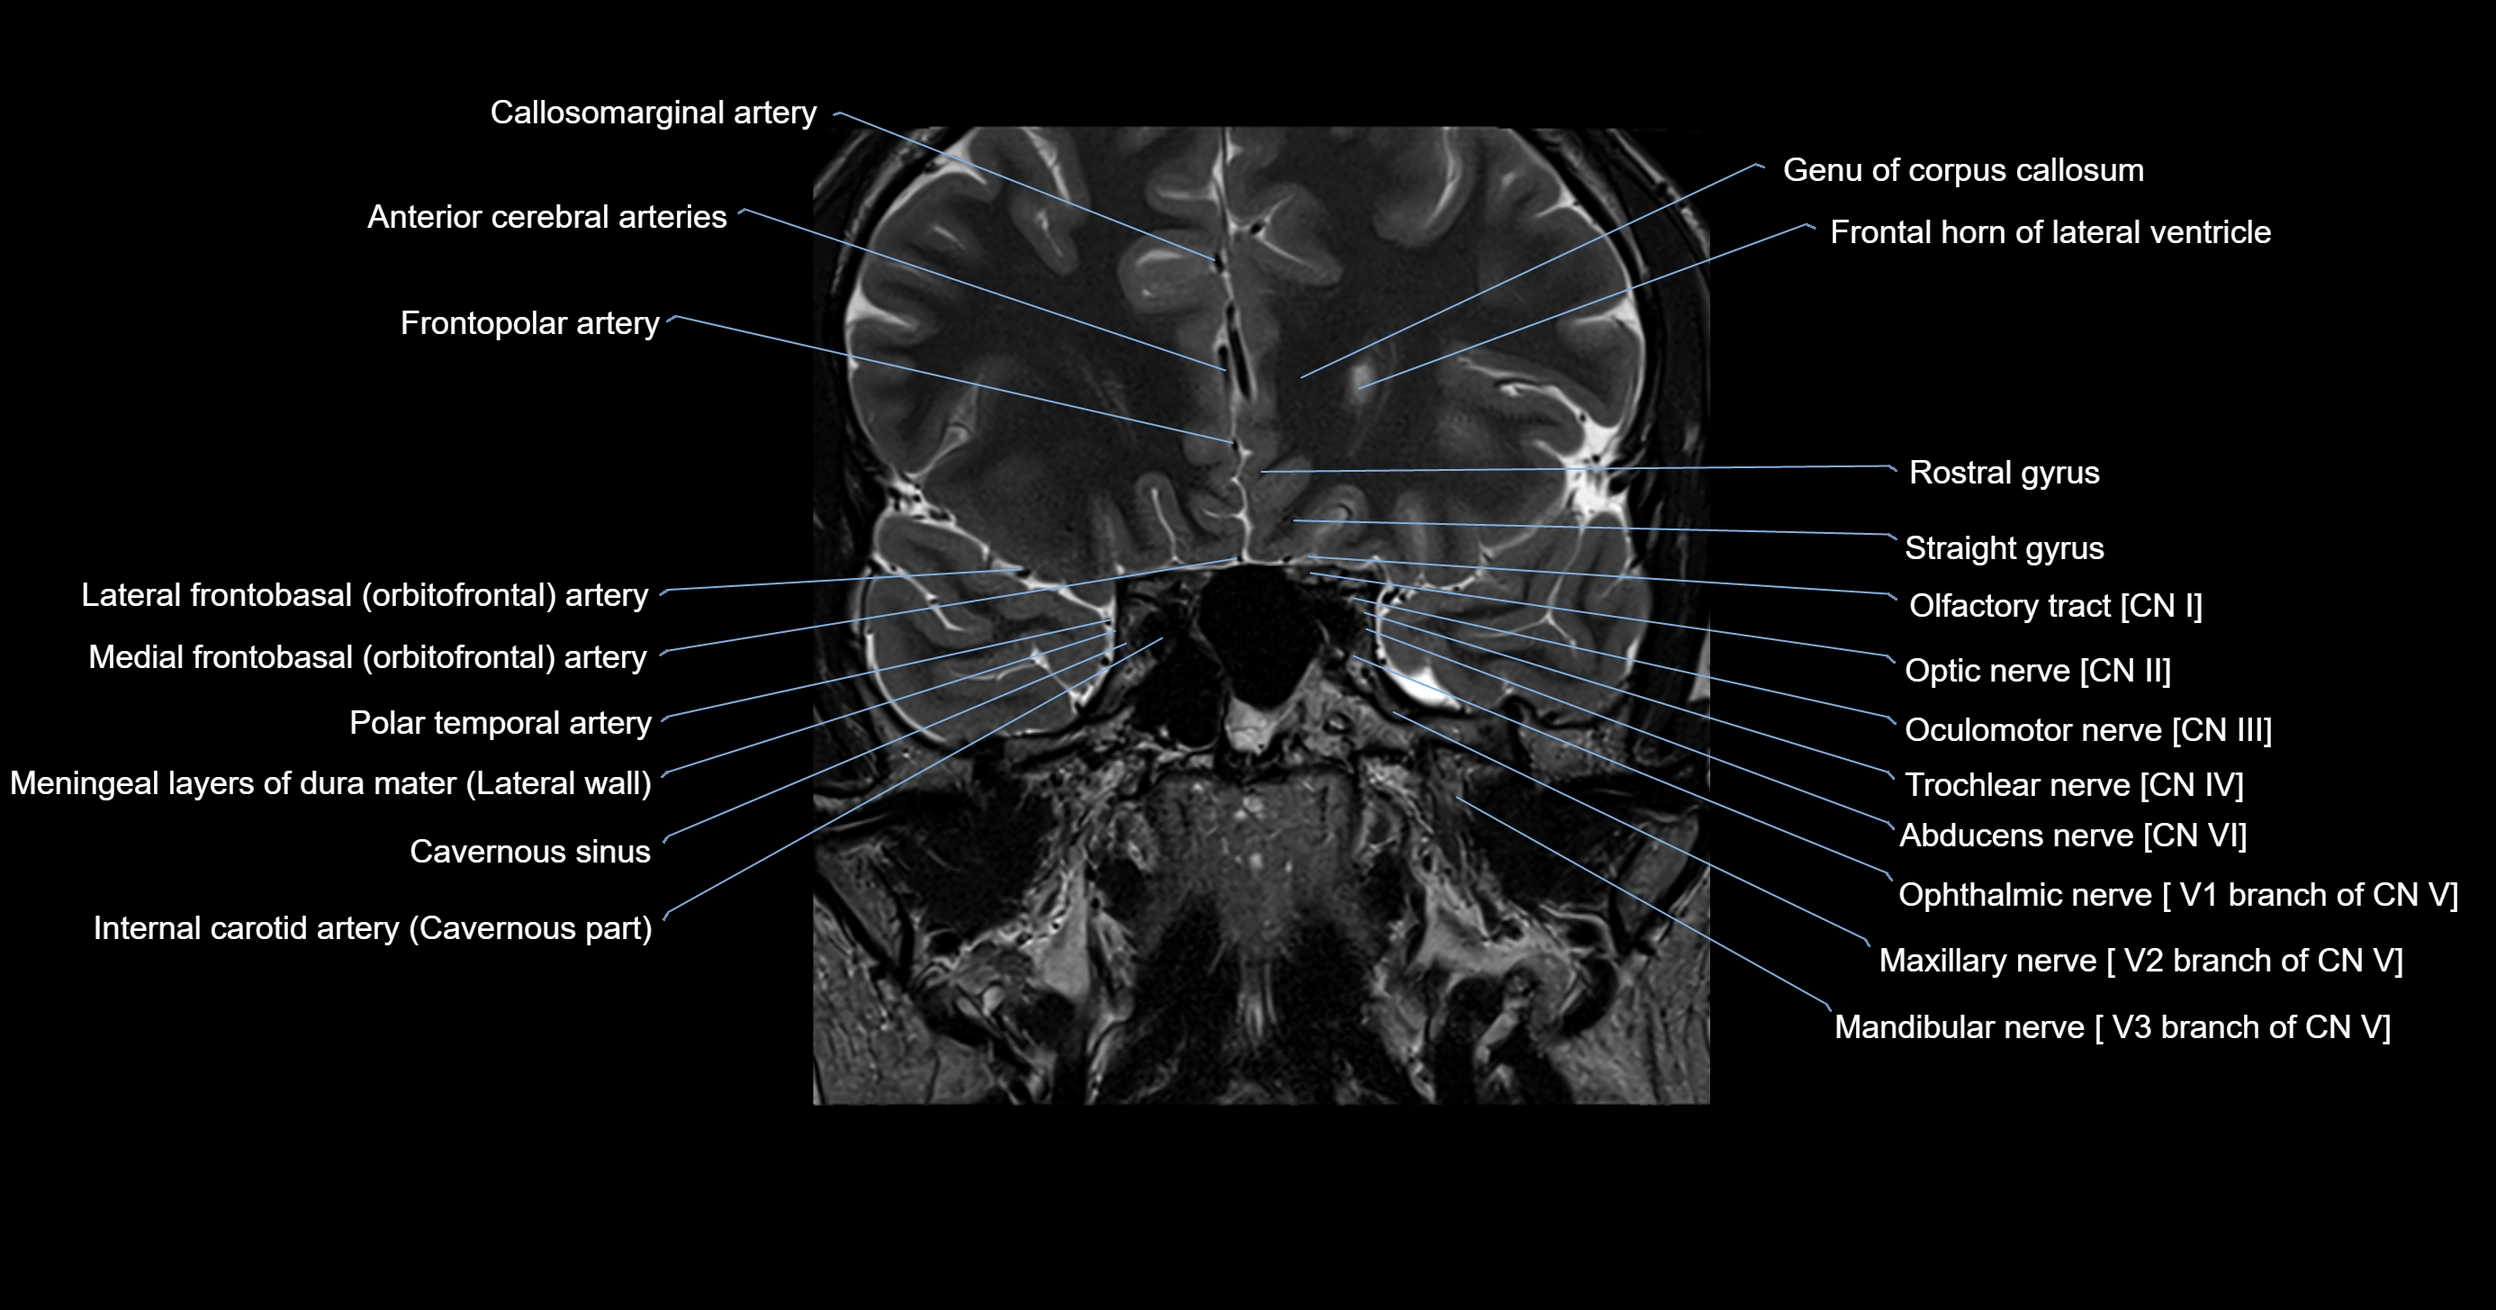

- Abducens nerve (Cranial nerve VI)

- Frontopolar artery

- Genu of corpus callosum

- Lateral frontobasal artery

- Mandibular nerve

- Maxillary nerve

- Oculomotor Nerve (Cranial Nerve III)

- Olfactory Nerve (Cranial Nerve I)

- Olfactory tract

- Optic Nerve (Cranial Nerve II)

- Polar temporal artery

- Rostral gyrus

- Trochlear nerve (Cranial nerve IV)

- cavernous sinus